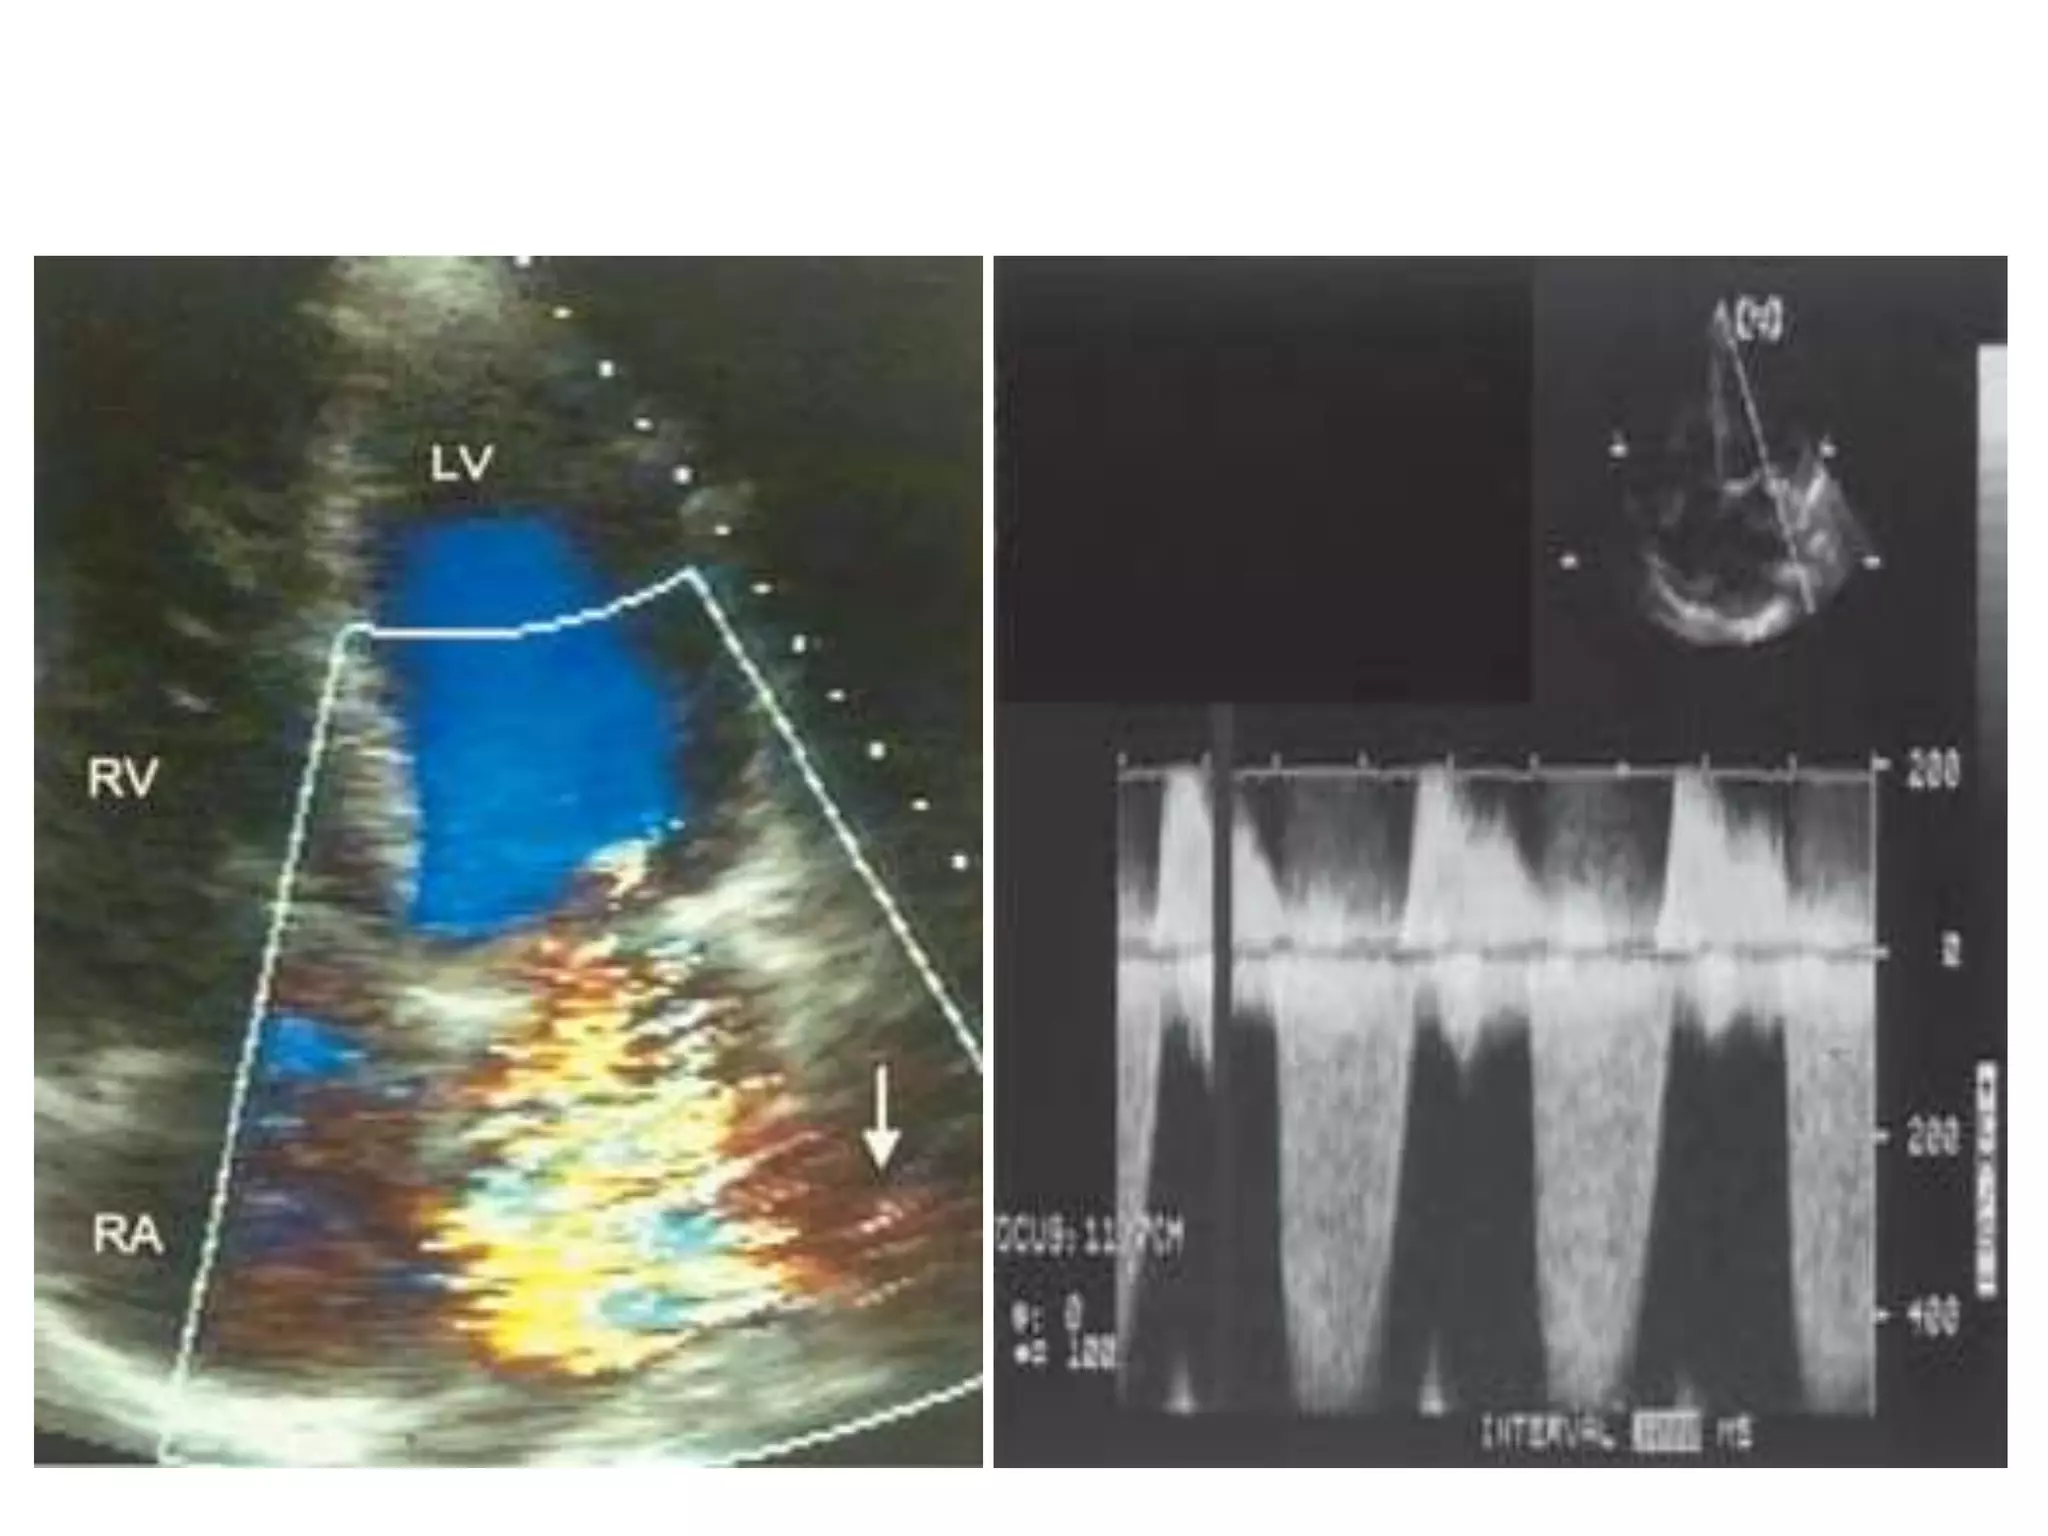

TR